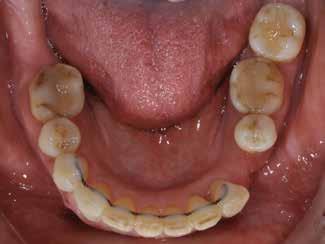

Patienttilfælde 1 (Fig. 1) er en 37-årig kvinde, henvist efter succesfuld behandling af stadie 3-parodontitis. Der er nu sundt

Før behandling

parodontium, ingen pocher over 4 mm, og både blødnings- og plakindeks er under 10 %. Patienten er motiveret for ortodontisk behandling, da hendes tænder er vandret over tid, delvist som følge af reduceret parodontium.

Der ses anterior trangstilling i begge kæber og overerupterede 1+1 og 2,1-1,2, hvilket resulterer i dybt bid med 2- tæt på ganepåbidning. Der er normale sidetandsrelationer, men der ses 5 mm horisontalt overbid (HOB) og 7 mm vertikalt

overbid (VOB). Papillen mellem 1+1 er betydeligt reduceret pga. fæstetab, og de mesialt kippede 1+1 har resulteret i en ”dark triangle”. Den facioorale funktion er for nuværende i.a. Panoramarøntgen (Fig. 1, I) viser marginalt knogletab i begge kæber og fravær af 8,7+7,8 og 8,7-8.

Objektivt anbefales behandling af det dybe bid, som ubehandlet forventes at forværres yderligere over tid. Patienten har ønske om behandling med æstetisk ortodontisk apparatur, alignere, og det vurderes muligt at behandle malokklusionen med alignere. Dog anbefales det generelt, at alignere undgås eller benyttes med væsentlige modifikationer af alignerens retention ved tandmobilitet, da dette ellers kan medføre jiggling, når aligneren tages af og på mange gange dagligt. På den anden side er der nogen evidens for, at alignerbehandling er associeret med bedre renhold og parodontal sundhed sammenlignet med fast apparatur (16).

Der planlægges alignerbehandling af begge kæber med intrusion af 1+1 og 2,1-1,2, nivellering af trangstilling UK med interproksimal reduktion (IPR) (Fig. 2 A, B) og senere IPR OK for reduktion af dark triangles mellem incisiverne efter nivellering. Patienten instrueres i at benytte alignere 20-22 timer/ dag med alignerskift hver 7. dag, og patienten ses hver 3.-8. uge under forløbet. Den første alignerserie består af 16 alignere for nivellering OK/UK og IPR i UK (Fig. 2). Efter denne serie planlægges IPR mellem incisiverne i OK for reduktion af dark triangles (Fig. 3) samt yderligere intrusion af OK og UK-fronten i 12 refinement-alignere. Patienten udviser god kooperation og er meget tilfreds med alignerapparaturet, som er mindre synligt end det faste apparatur (Fig. 4).